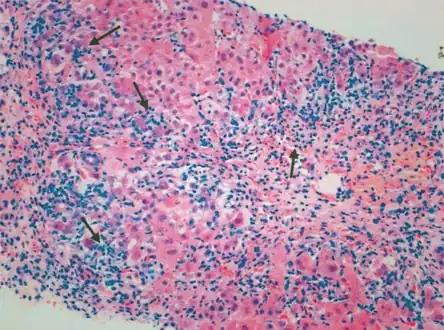

Portal and periportal inflammatory infiltrate- interface hepatitis (piecemeal necrosis) arrow(s)